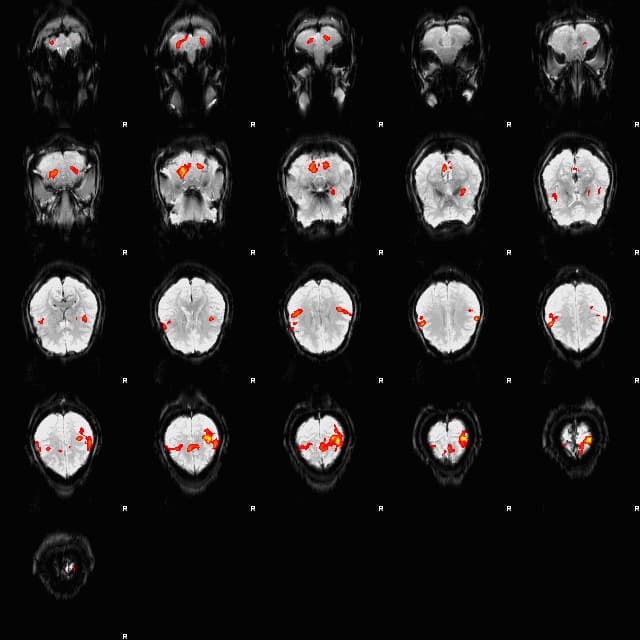

Blood-oxygen-level-dependent imaging, or BOLD-contrast imaging, is a method used in functional magnetic resonance imaging (fMRI) to observe different areas of the brain or other organs, which are found to be active at any given time. Neurons do not have internal reserves of energy in the form of sugar and oxygen, so their firing causes a need for more energy to be brought in quickly. Through a process called the haemodynamic response, blood releases oxygen to active neurons at a greater rate than to inactive neurons. This causes a change of the relative levels of oxyhemoglobin and deoxyhemoglobin (oxygenated or deoxygenated blood) that can be detected on the basis of their differential magnetic susceptibility. In 1990, three papers published by Seiji Ogawa and colleagues showed that hemoglobin has different magnetic properties in its oxygenated and deoxygenated forms (deoxygenated hemoglobin is paramagnetic and oxygenated hemoglobin is diamagnetic), both of which could be detected using MRI. This leads to magnetic signal variation which can be detected using an MRI scanner. Given many repetitions of a thought, action or experience, statistical methods can be used to determine the areas of the brain which reliably have more of this difference as a result, and therefore which areas of the brain are most active during that thought, action or experience. Although most fMRI research uses BOLD contrast imaging as a method to determine which parts of the brain are most active, because the signals are relative, and not individually quantitative, some question its rigor. Other methods which propose to measure neural activity directly have been attempted (for example, measurement of the Oxygen Extraction Fraction, or OEF, in regions of the brain, which measures how much of the oxyhemoglobin in the blood has been converted to deoxyhemoglobin), but because the electromagnetic fields created by an active or firing neuron are so weak, the signal-to-noise ratio is extremely low and statistical methods used to extract quantitative data have been largely unsuccessful so far.